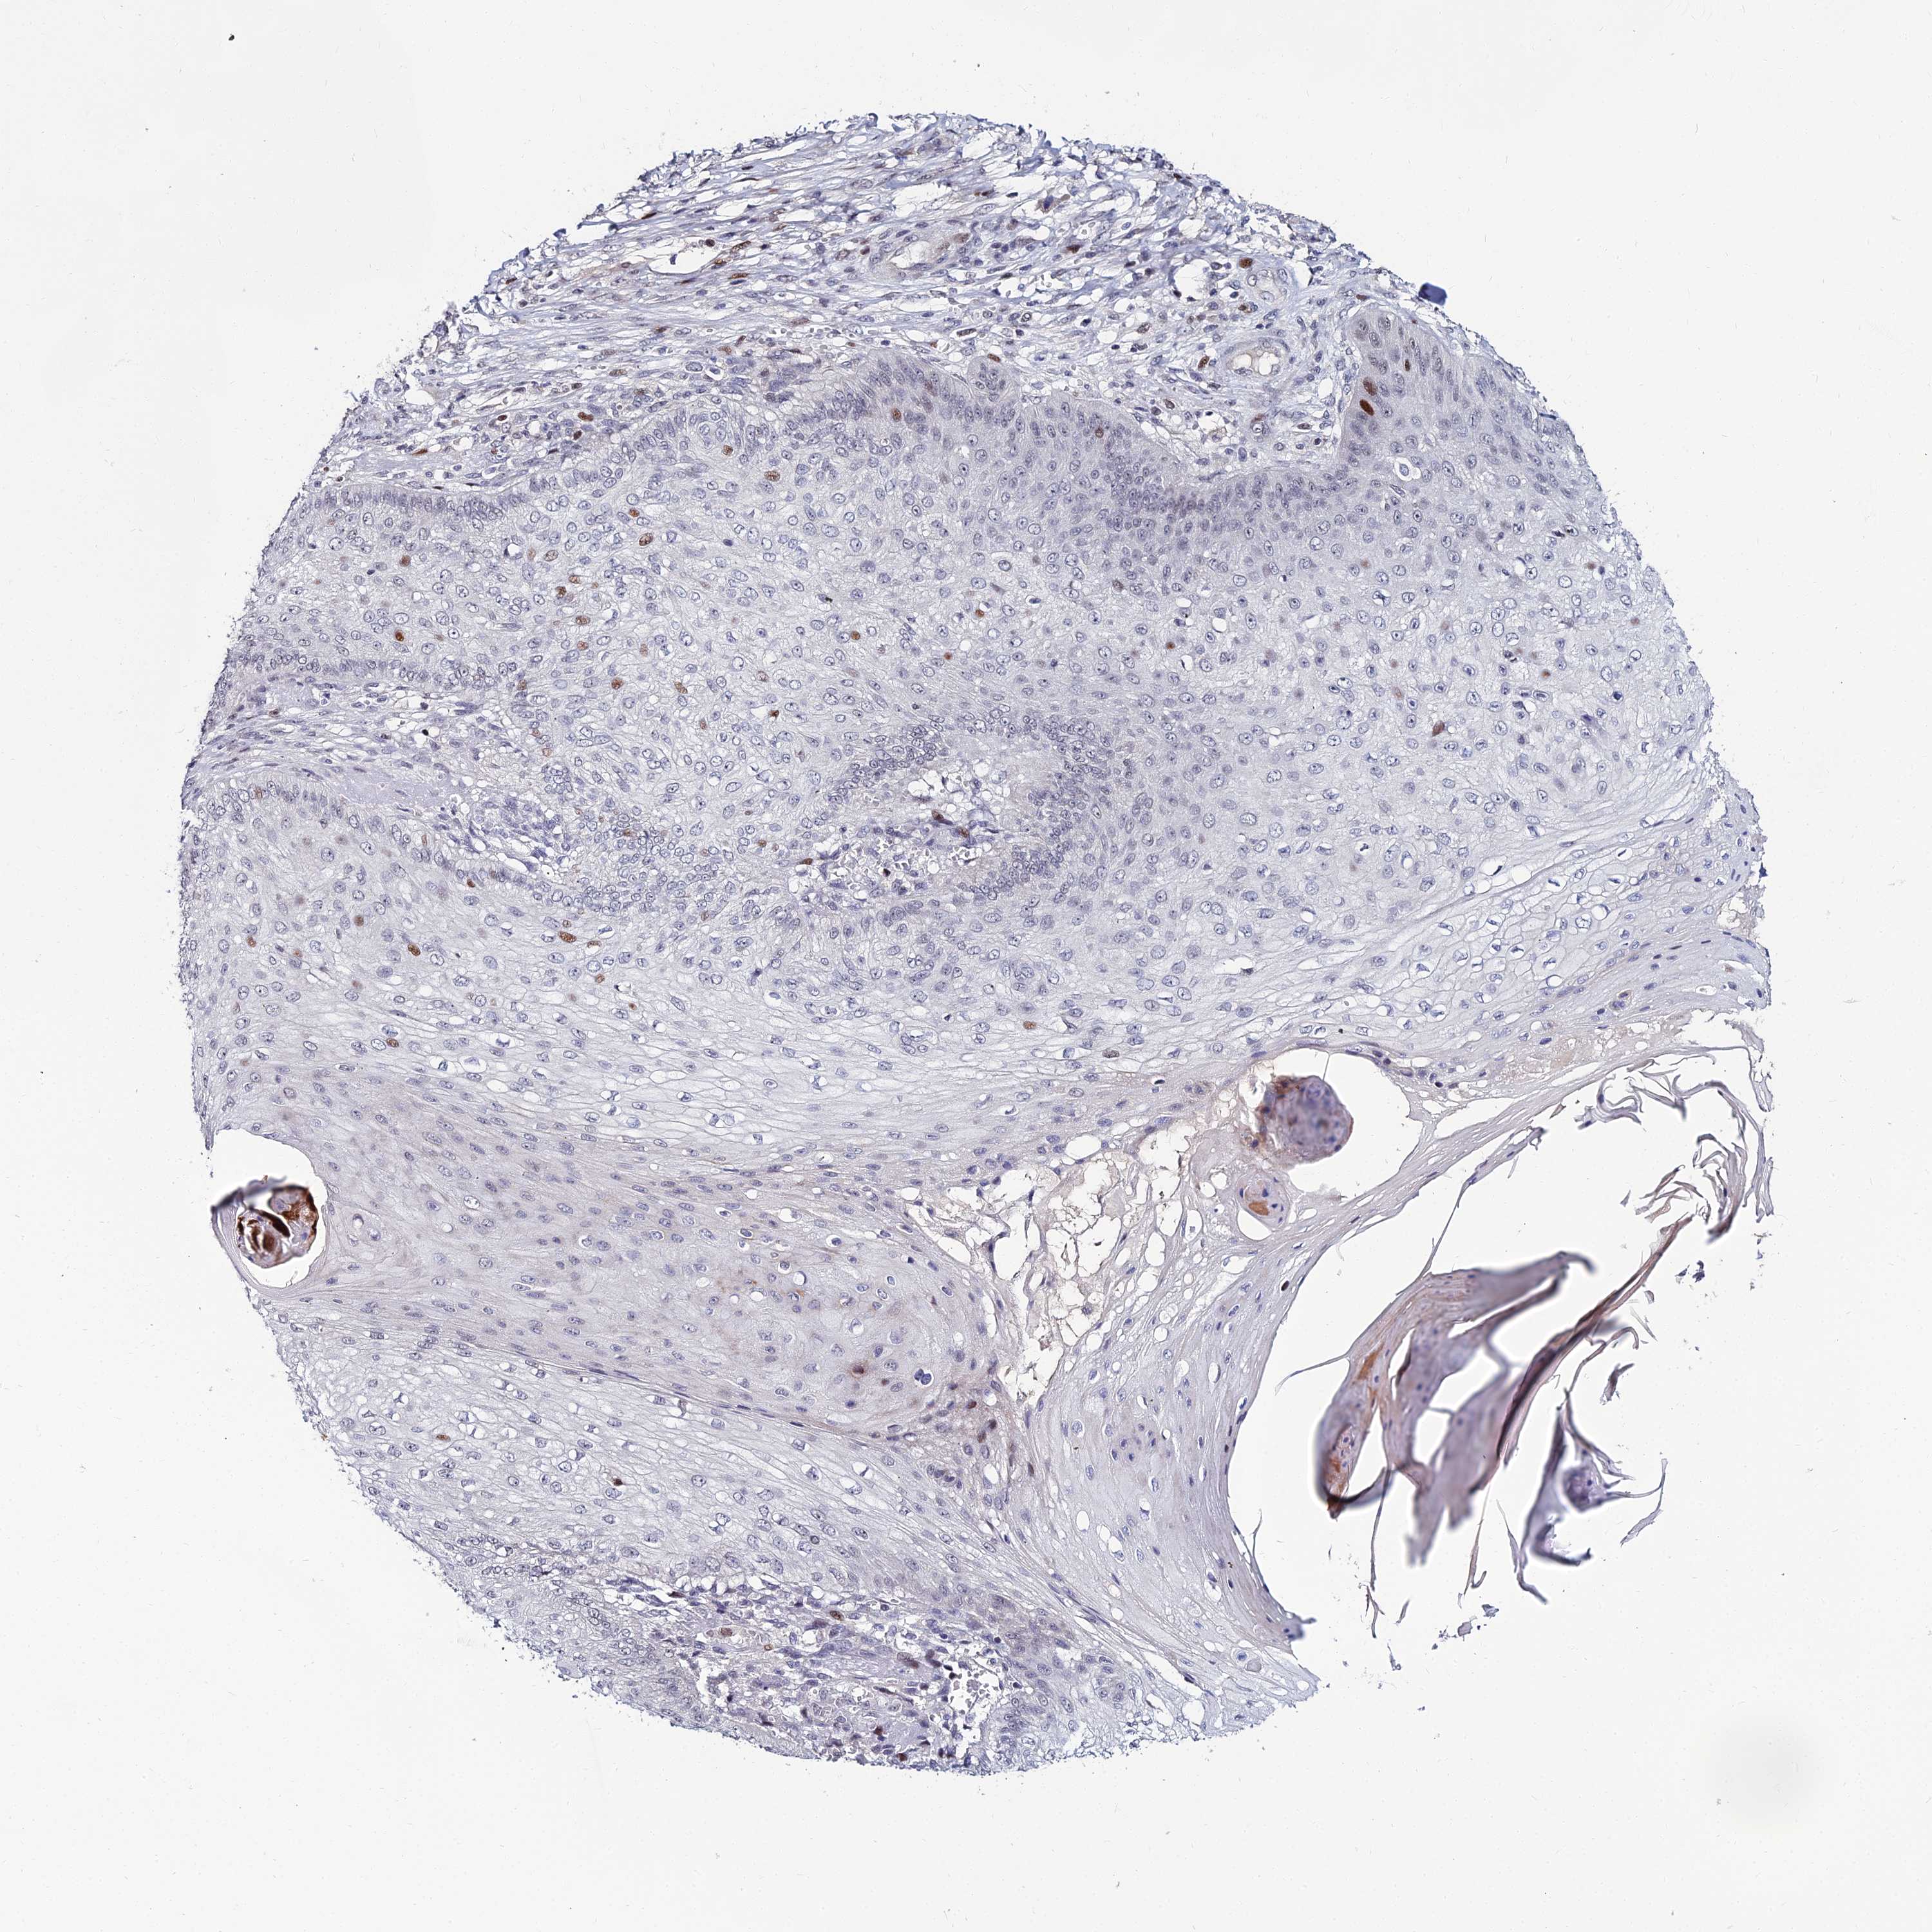

SKIN CANCER - Protein expressioni

A mouse-over function shows sample information and annotation data. Click on an image to view it in a full screen mode. Samples can be filtered based on level of antibody staining by selecting one or several of the following categories: high, medium, low and not detected. The assay and annotation is described here.

Antibody stainingi

Antibody staining in the annotated cell types in the current human tissue is reported as not detected, low, medium, or high, based on conventional immunohistochemistry profiling in selected tissues. This score is based on the combination of the staining intensity and fraction of stained cells.

Each image is clickable and will lead to virtual microscopy that enables deeper exploration of all samples and also displays staining intensity scores, fraction scores and subcellular localization as well as patient and tissue information for each sample.

Antibody HPA045275

Staining

Medium

Intensity

Weak

Quantity

<25%

Location

Nuclear

Squamous cell carcinoma, NOS